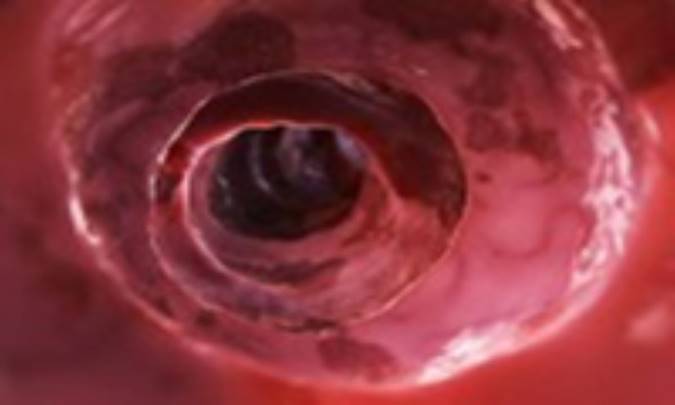

علائم عفونت کولون

عفونت کولون می‌تواند طیف وسیعی از علائم مانند اسهال خونی را موجب شود. این مقاله اطلاعاتی را در مورد علائم متداول این بیماری فراهم ساخته است.

کولون colon و یا روده بزرگ آخرین ناحیه از دستگاه گوارش می‌باشد. وظیفه‌ی اصلی کولون (قسمتی از روده‌ی بزرگ)، جذب رطوبت و نمک از پسمانده‌های مواد غذایی پیش از دفع توسط بدن است. هر چند کولون مسئول جذب مواد مغذی نیست، اما نقش بسیار مهمی در جذب آب، پتاسیم و ویتامین‌های محلول در چربی دارد. کولون انسان متشکل از چهار بخش است؛ کولون صعودی یا بالا رونده، کولون عرضی، کولون نزولی یا پایین رونده، و کولون سیگموئید.